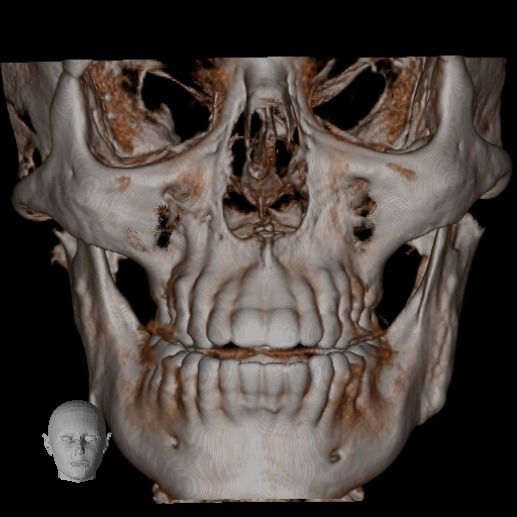

El Centro Radiológico Diagnóstico Oral 3D, es una empresa antioqueña que ofrece a sus pacientes desde el año 2009, tecnología de vanguardia en radiografías tridimensionales con calidad fotográfica. Las posibilidades para mejorar la eficacia en los diagnósticos bucales son evidentes, también lo son las posibilidades de manipulación de imagen. El sistema de imágenes en 3D ofrece detalles sin precedentes, convirtiéndola en la opción idónea para la mayoría de aplicaciones odontológicas, incluyendo implantes, tratamiento de conductos, ortodoncia, odontopediatría, periodoncia y cirugía

El mayor beneficiado con el uso de esta tecnología es el paciente, el cual podrá ser evaluado en todas sus dimensiones con una baja dosis de radiación, con un costo accesible y sin contaminar  el medio ambiente. Dependiendo de la necesidad del paciente, hay varios tipos de tomografías y los especialistas en el área odontológica hacen uso de ellas según su especialidad.

La radiología oral especializada es fundamental para una práctica dental integral, proporcionando información específica que influye en la toma de decisiones clínicas y mejora los resultados del tratamiento para los pacientes

Evaluación de patologías dentales y maxilofaciales

Planificación de tratamientos ortodónticos y ortognáticos